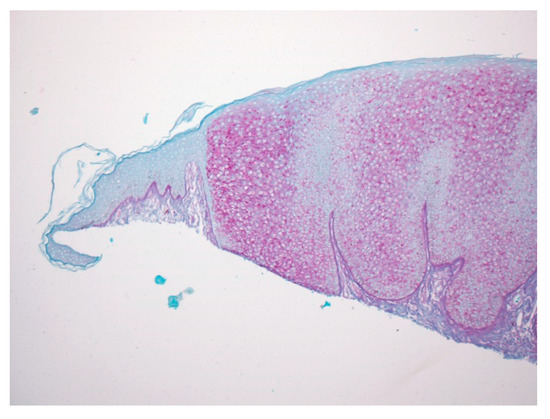

Figure 1.

A dome-shaped lesion exhibits pale keratinocytes with a large perinuclear vacuole reminiscent of trichilemmal differentiation.

Figure 3.

With PAS staining, the lesion is sharply demarcated from the normal epidermis, suggesting glycogen accumulation in lesional keratinocytes.